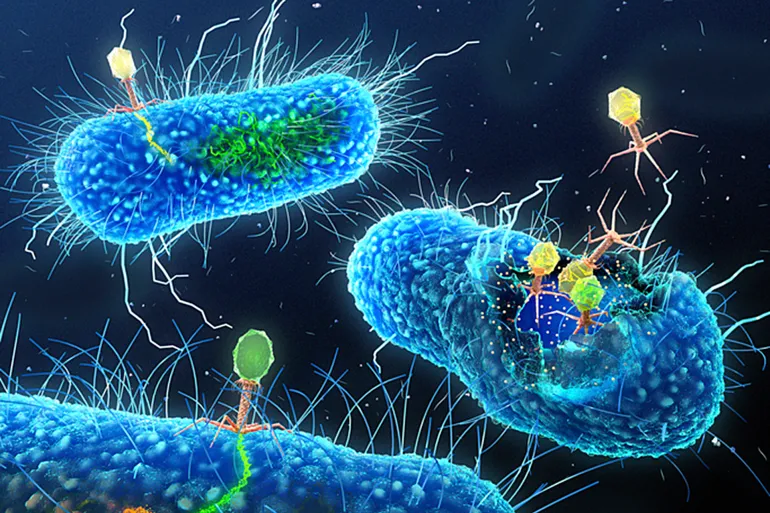

علماء يصنعون فيروسات من الصفر لتعمل “قاتلة مأجورة” ضد البكتيريا

أعلن باحثون من شركة “نيو إنجلاند بايولابس” وجامعة ييل عن تطوير طريقة تتيح تصميم عاثيات، وهي فيروسات تصيب البكتيريا، ثم…